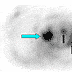

Axial FDG-PET image (at approximately the same level as the axial neck CT in Figure 4) shows focal intense FDG uptake in the lateral aspect of the left laryngeal region corresponding to the supraglottic mass at this site (red arrow). There are no other FDG-avid foci in the neck, including in the region of the borderline level III lymph node on the left (as seen in Figure 5).